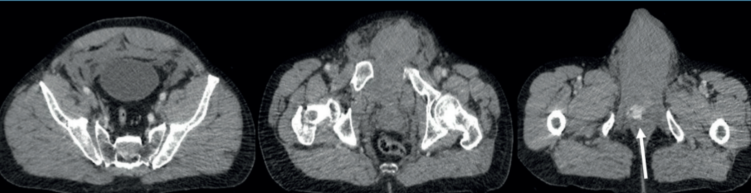

La tomografía computada evidenció diástasis de la sínfisis púbica de 5 cm, fractura lineal completa intertrocantérica derecha, fractura perpendicular del ala ilíaca derecha con desplazamiento posterior. Disrupción sacroilíaca izquierda. Líquido libre prevesical en espacio de Retzius y Bogros, continúa a bolsa escrotal, con un volumen estimado mayor de 500 ml. Con pequeña área de realce correspondiente a extravasación de contraste (figura 1) y (figura 2). Cráneo, tórax y abdomen sin lesiones. Se procedió a fijación externa de la pelvis.

Figura 2: Tomografía computada de pelvis con contraste intravenoso. Evidencia líquido libre prevesical en el espacio de Retzius y Bogros, que continúa hasta la bolsa escrotal. En la tercera imagen se observa una pequeña área de realce que corresponde a extravasación de contraste como signo de sangrado activo (flecha blanca).